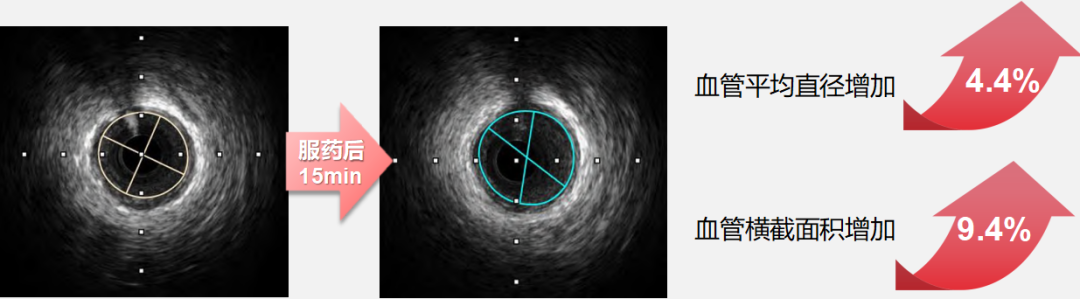

• 而速效救心丸展现出 “精准化” 的血管调控特征:对直径 2.00-2.75mm 的细小冠状动脉扩张作用更突出,服药后15 分钟该直径区间血管横截面积面积扩张百分比最高可达 8.58%(如下图),且扩张过程中患者血压、心率等血流动力学指标无显著波动。

图片